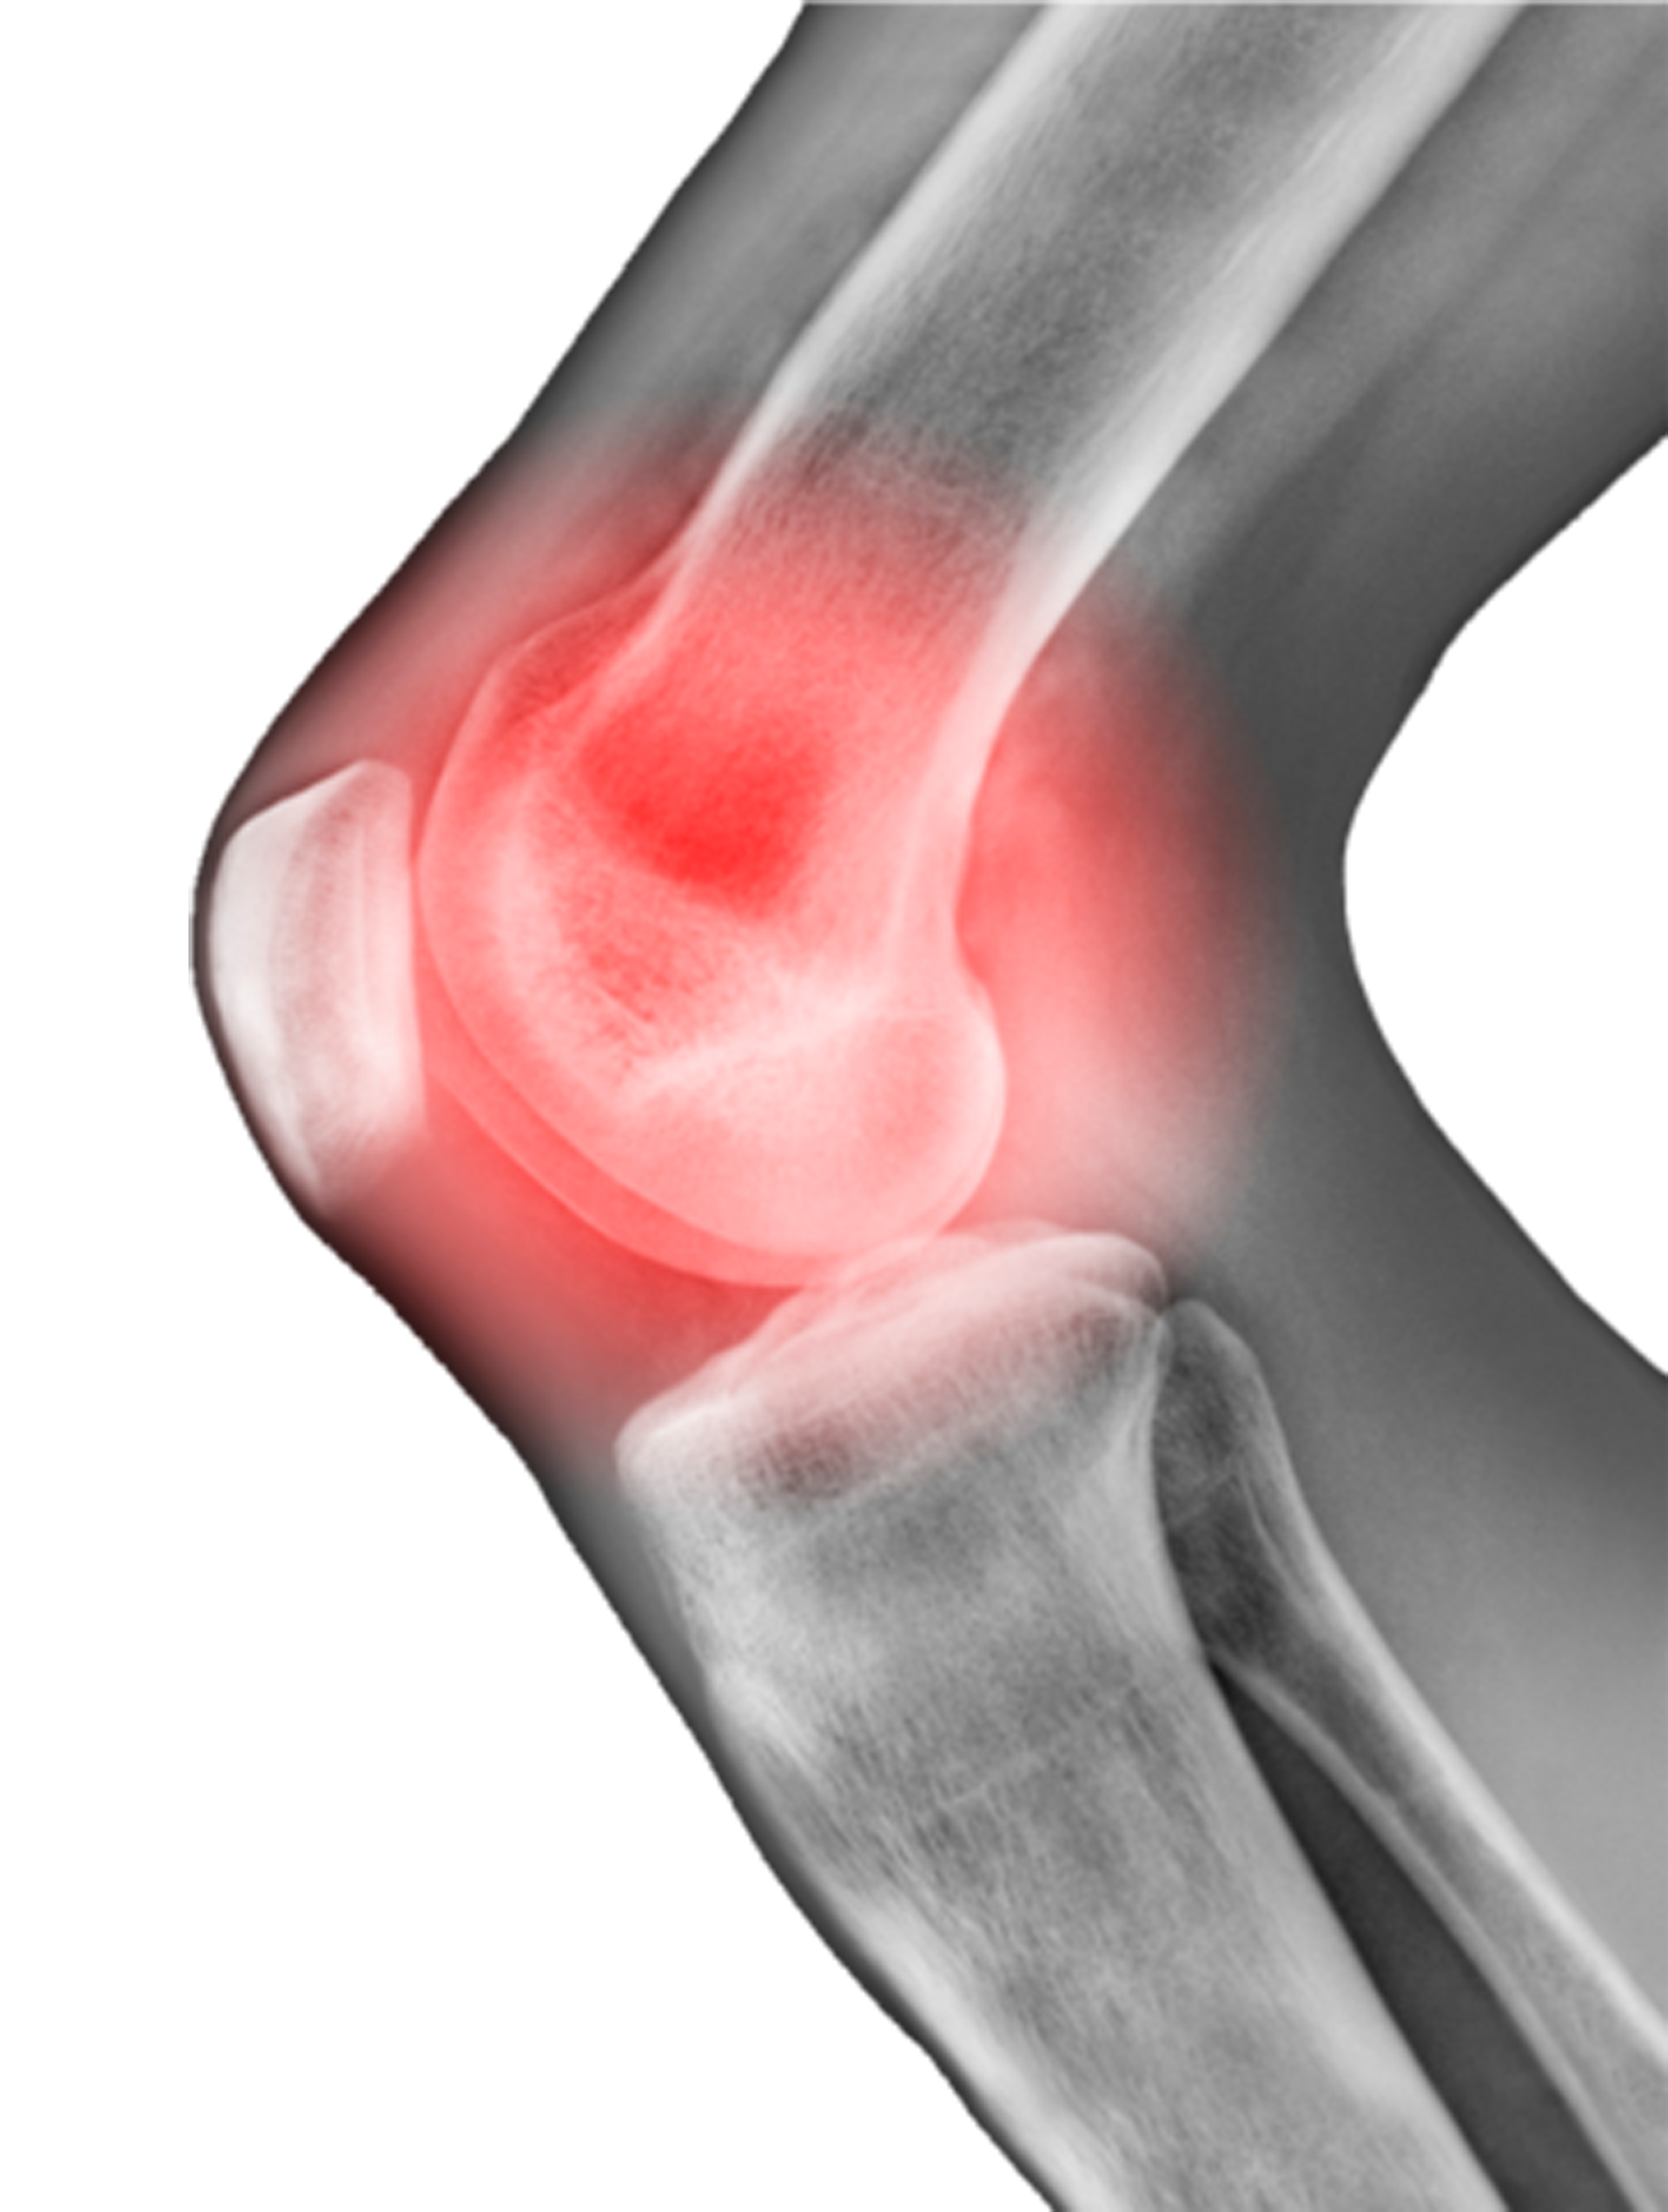

osteoarthritisknee London Bridge Orthopaedics Osteoarthritis Knee Age 40 By stage 4, however, they may experience mobility issues and. About 40 percent of people with the. An increase of 113% since 1990 (1). As we grow older, the cartilage in the knee joint starts to gradually wear. The most common cause of osteoarthritis of the knee is age. Knee osteoarthritis is a progressive disease, meaning it tends to slowly. Osteoarthritis Knee Age 40.